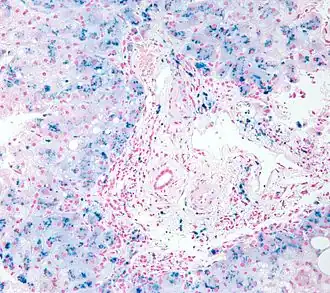

![]() Биопсия: гистологическая картина гемосидероза. | |